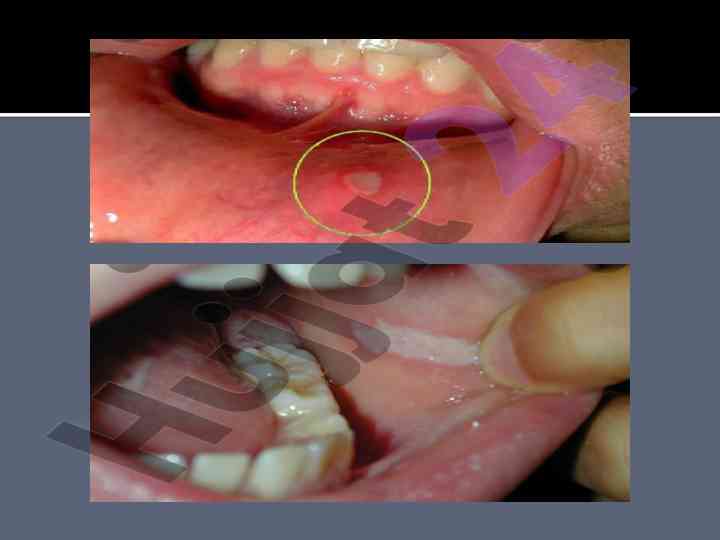

Og’iz bo’shlig’ini protezlashga tayyorlash

ADTI stomatologiya fakulteti talabasi tomonidan tayyorlangan mustaqil ishda og’iz bo’shlig’ini protezlashga tayyorgarlik jarayonlari, terapevtik va xirurgik tayorgarlik haqida ma'lumotlar berilgan.